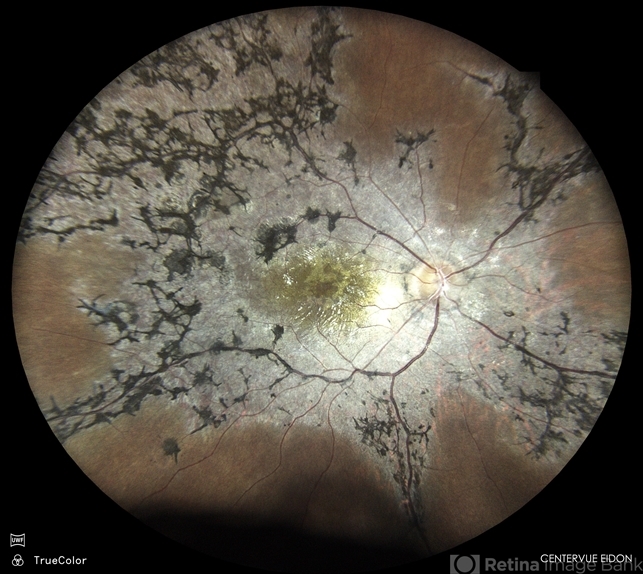

- retinitis pigmentosa, RP, RP variant

- Dr. Akansha Sharma, Bharati Eye Hospital

- Scanning laser ophthalmoscope

- Color fundus photograph of a 30 year old male with retinitis pigmentosa.